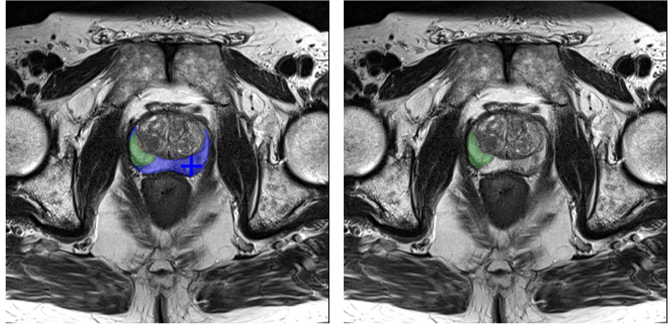

Refer to caption

Figure 5: An illustrative example of the automated trajectory generation process for liver segmentation. The algorithm progressively refines the predicted mask through iterative interactions.

For each iteration (e.g., Step 0), two visualization panels are presented: (1) The

first image displays the current segmentation state, showing the predicted mask (green translucent overlay) generated by the current click (marked by a green star). (2) The second image illustrates the error analysis against the Ground Truth (delineated by a green outline). The differences are visualized as blue translucent regions for False Negatives (FN, under-segmentation) and red translucent regions for False Positives (FP, over-segmentation). The star in this panel indicates the calculated next action based on the largest error region: a blue star denotes a Positive Click (P) to correct under-segmentation, while a red star denotes a Negative Click (N) to correct over-segmentation.